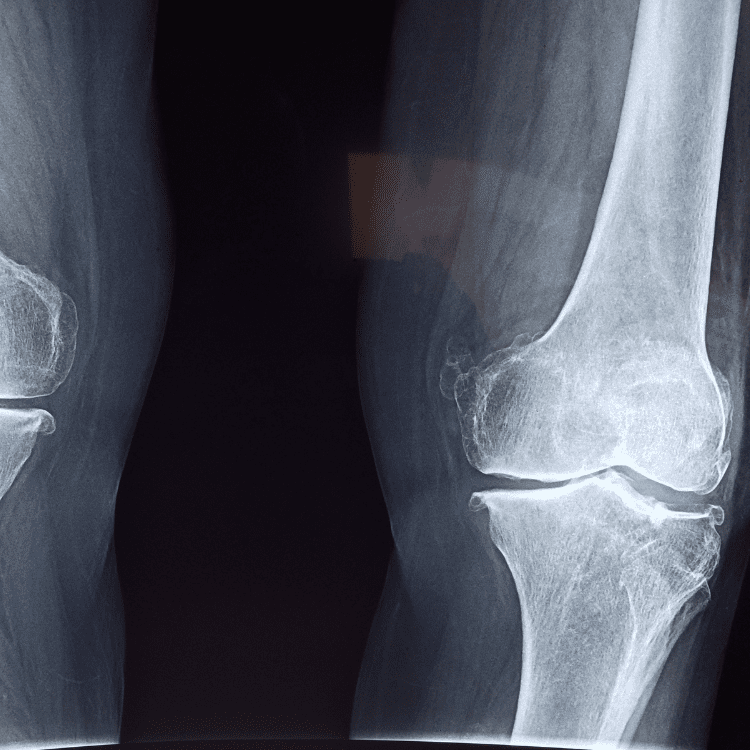

Algunos tumores pueden observarse inicialmente como lesiones “silenciosas” en radiografías o estudios de imagen solicitados por otras razones.

El diagnóstico de tumores óseos combina historia clínica, exploración física e imagenología avanzada.